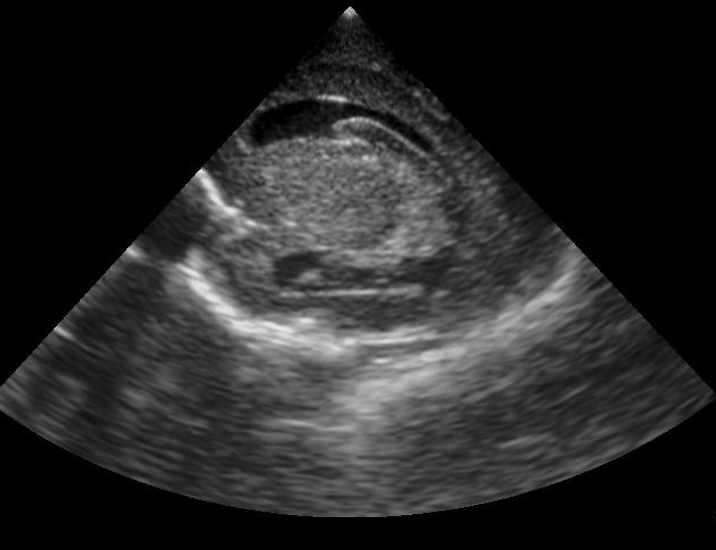

Neonatology Grade 2 IVH Pitfall 1 Image